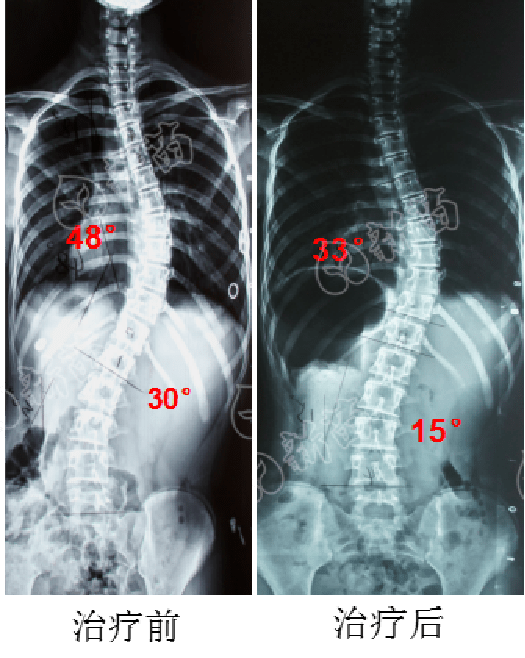

保守案例通过努力13岁女孩48侧弯锐减15成功避免开刀

图片尺寸525x658